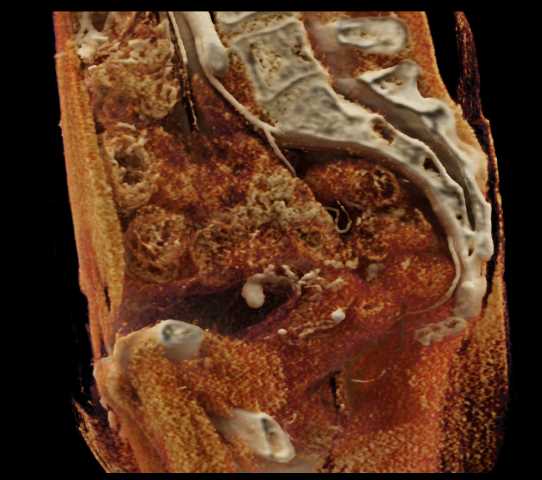

Urachal Carcinoma of the Bladder